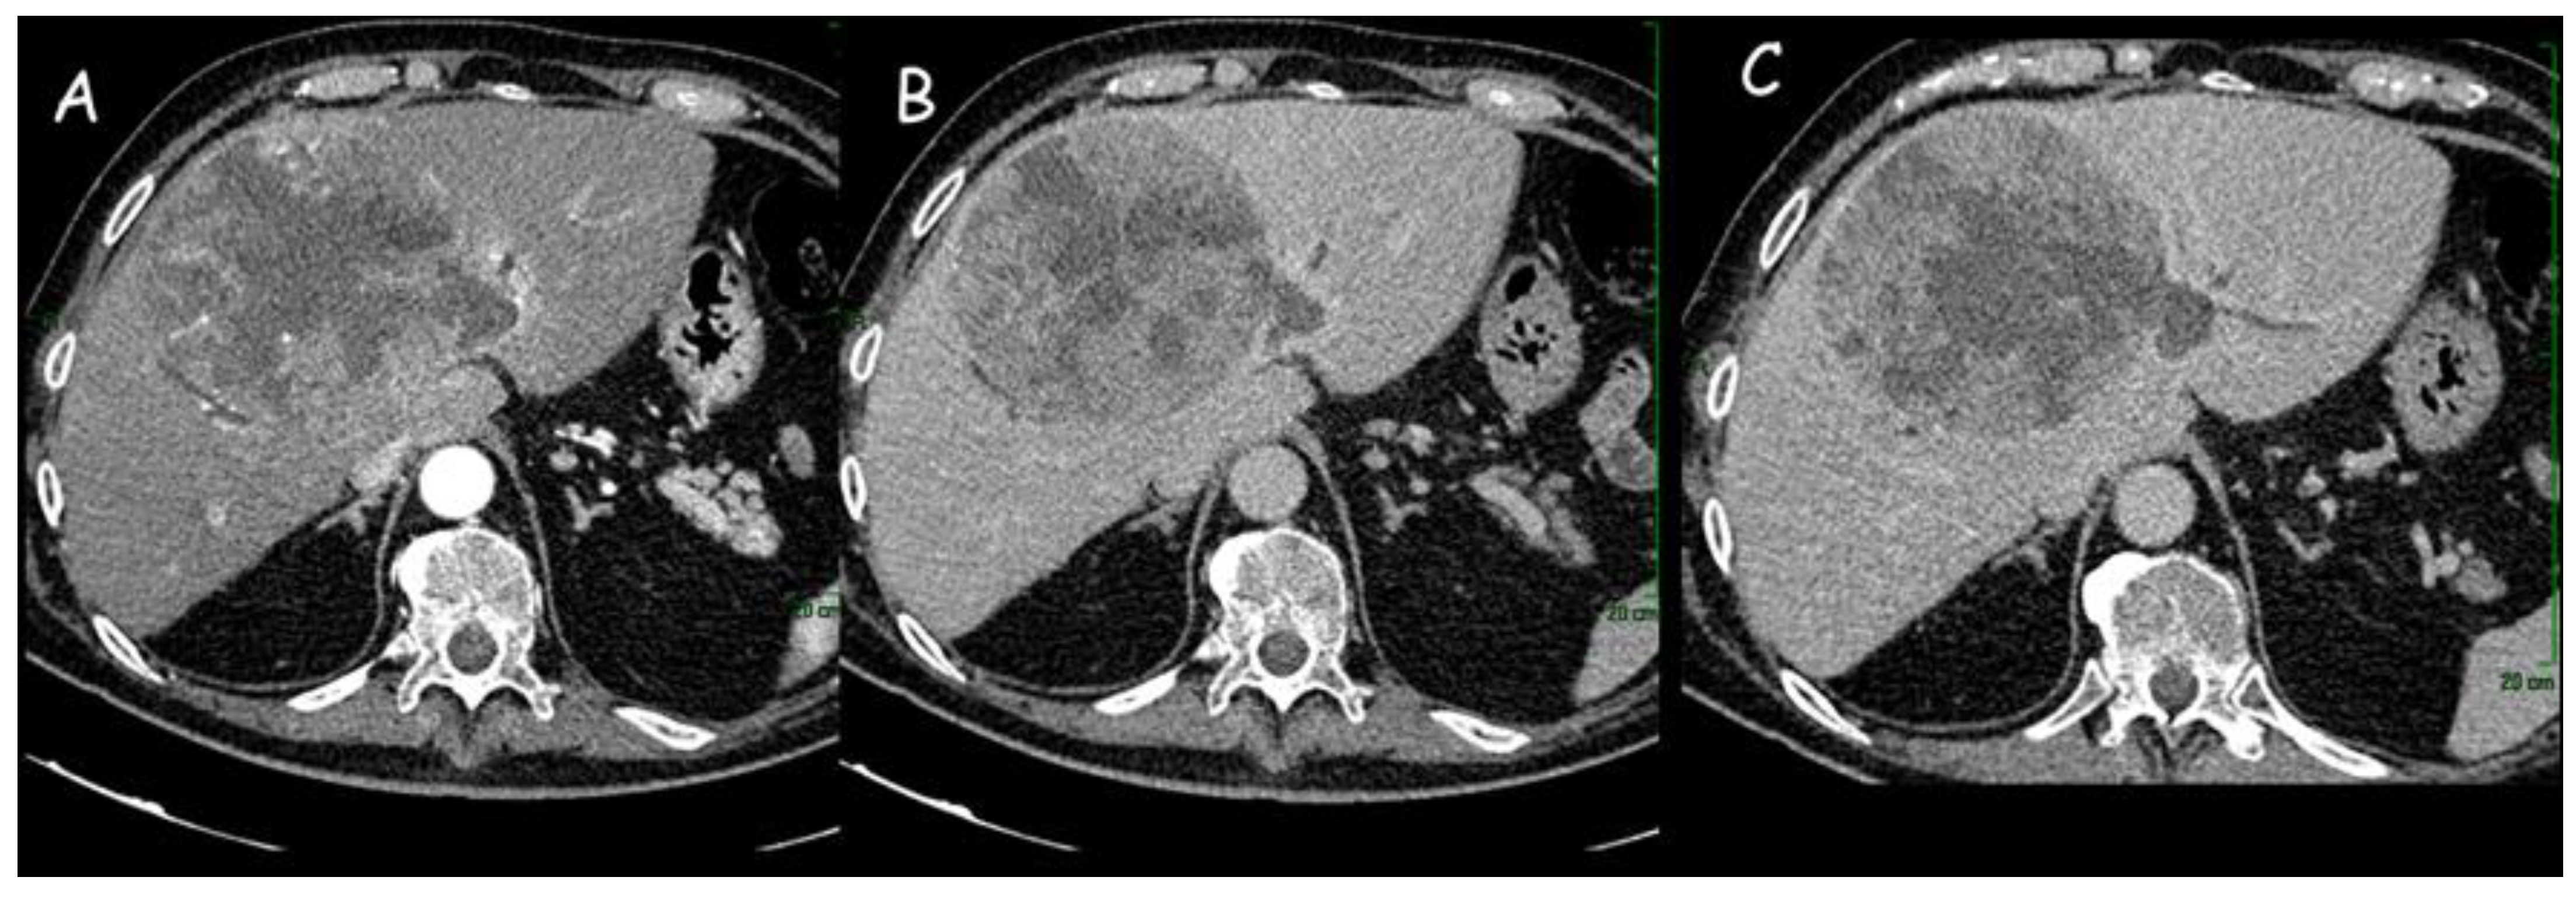

Figure 1.

(A,B) Computed tomography imaging of intrahepatic cholangiocarcinoma (12 cm × 11 cm) of the right liver lobe: dishomogeneous enhancement in the arterial phase with hypodense areas of intralesional necrosis. (C) Dilatation of the peripheral intrahepatic biliary ducts.

(A,B) Computed tomography imaging of an intrahepatic cholangiocarcinoma of approximately 8 cm in the left hepatic lobe, with capsular retraction, central hypodensity, and inhomogeneous enhancement due to necrotic-colliquative phenomena. Peripheral rim enhancement in the arterial phase (A) with progressive contrast filling in the subsequent phases (B). (C) Locoregional lymph nodes (white arrow).

The contrast enhancement pattern of the lesion is important, especially for the differential diagnosis with HCC: iCCA receives its blood supply from portal vein branches and, for this reason, presents portal or delayed-phase enhancement pattern, whereas HCC blood supply comes from hepatic arteries with a consequent arterial-phase enhancement pattern [24]. The principal distinctive feature of iCCA, due to the abundant cellularity in the peripheral parts of the neoplastic mass, is represented by the initial rim enhancement or the peripheral enhancement in the arterial phase with subsequent centripetal enhancement in the delayed phase [25]. This phase, which starts about 3–5 min after contrast agent injection, is essential for iCCA diagnosis and is characterized by a marked central enhancement due to the presence of abundant fibrotic tissue [23].